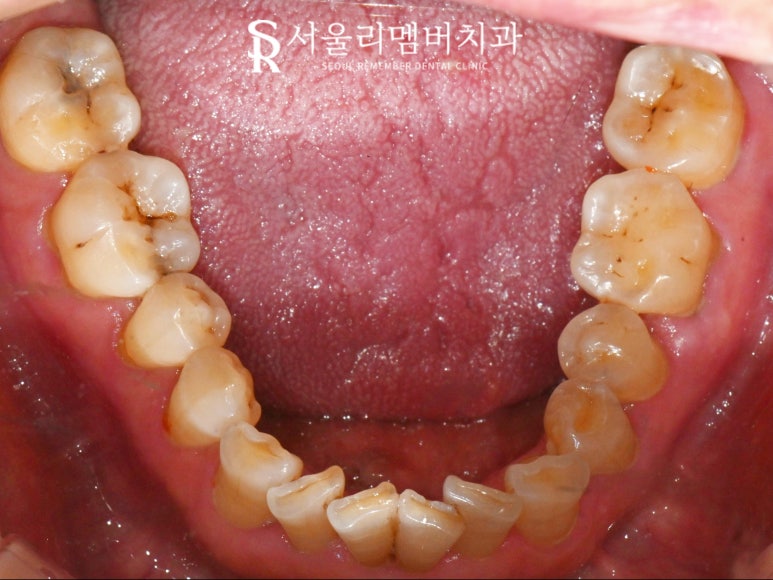

먼저 전체적인 구강 상태 파악을 위해

입안을 살펴보겠습니다.

2024.07.11

하악 어금니 교합면의 깊은 굴곡을 따라

충치가 생겨있는 곳이 존재하고

눈에 잘 보이지 않는

미세한 금으로 찌릿한 통증을 유발하는

치아도 존재했습니다.